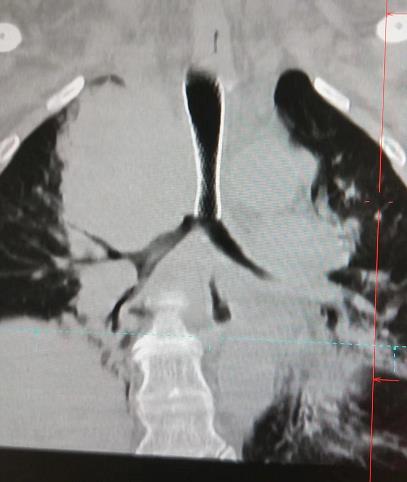

入院進行相關的檢查,肺部CT檢查結果顯示:由于縱隔上的腫瘤壓迫患者氣管導致狹窄呼吸困難,找到張先生病灶原因后,牛院長帶領醫療團隊經過多次閱片、討論,一致認為目前最先要解決的是困擾張大叔的呼吸問題,時間拖得越久就容易出現呼吸、心跳驟停的可能。

2020年4月8日,牛院長團隊通過DSA+CT技術不僅快速準確找到狹窄的支氣管,還更為清楚地看到腫瘤及其他周圍組織的關系。在氣管鏡下,牛院長熟練進行著進導絲、送置入器、釋放支架等等步驟;隨后在微波射頻消融設備下,將穿刺針刺入縱膈上的腫瘤部位,利用射頻發熱原理使腫瘤部位壞死。歷時一個半小時手術順利結束。

DSA+CT可以通過將兩種二維圖象融合成三維圖象,全方位了解病灶的血供情況,確保靶病灶得到有效治療。

比起單一的檢查,DSA+CT能更為清楚地顯示腫瘤及其他周圍組織的關系,保證靶病灶得到有效治療,而周圍正常臟器不受損傷,確保介入手術的安全性,最大程度地減少并發癥。